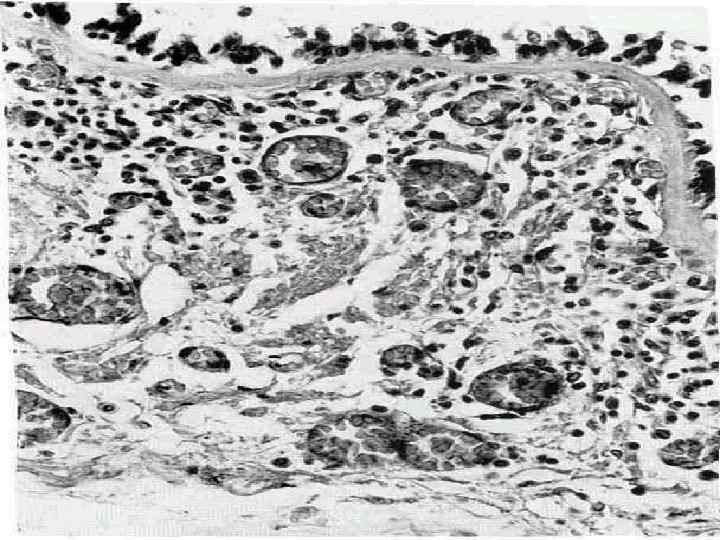

ОПРЕДЕЛЕНИЕ • Астма — хроническое воспалительное заболевание дыхательных путей, в котором принимают участие многие клетки: тучные клетки, эозинофилы и Т лимфоциты У предрасположенных лиц это воспаление приводит к повторяющимся эпизодам хрипов, одышки, тяжести в грудной клетке и кашлю, особенно ночью и/или ранним утром. Эти симптомы обычно сопровождаются распространенной обструкцией бронхиального дерева, которая обратима спонтанно или под влиянием лечения.

Бронхиальная астма, вне зависимости от степени тяжести, хроническое воспалительное заболевание дыхательных путей, которое сопровождается симптомами гиперреактивности и формированием обструкции четырех типов: • Спазм гладких мышц бронхов острый тип • Отек слизистой дыхательных путей подострый тип • Образование вязкого секрета, обтурирующего терминальные отделы дыха тельных путей хронический тип • Склеротические изменения в стенке бронхов, которые необратимы.